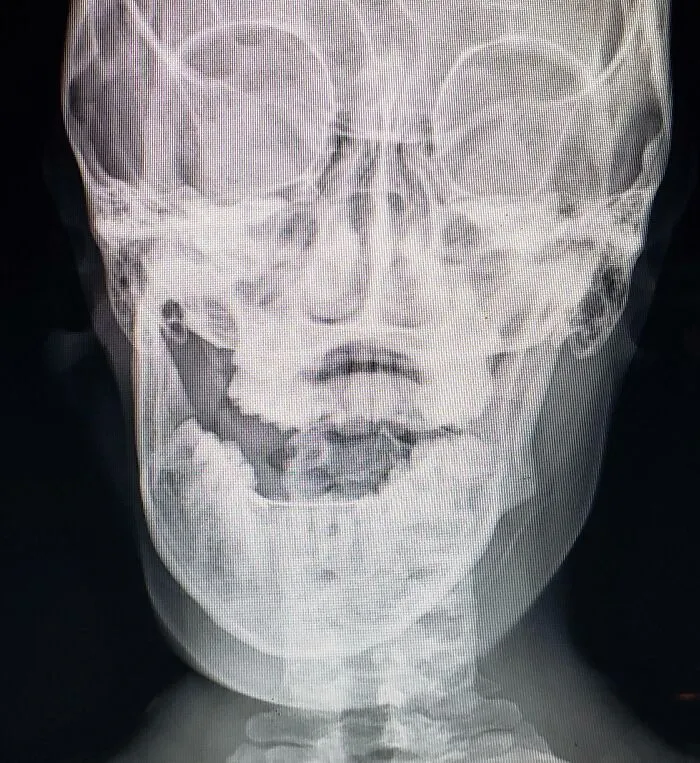

«Всегда проверяйте наушники». «Всегда проверяйте наушники».© Fears I Never Knew I Had Как это могло случиться? Как это могло случиться?© Fears I Never Knew I Had Какой кошмар. Какой кошмар.© Fears I Never Knew I Had «Недавно во время обеденного перерыва я ел нектарин, и когда я сделал очередной укус, косточка раскрылась, обнажив колонию муравьев». «Недавно во время обеденного перерыва я ел нектарин, и когда я сделал очередной укус, косточка раскрылась, обнажив колонию муравьев».© Fears I Never Knew I Had «Надеемся, что с ней все в порядке». «Надеемся, что с ней все в порядке».© Fears I Never Knew I Had «Банкомат отключился с моей картой в нем». «Банкомат отключился с моей картой в нем».© Fears I Never Knew I Had «О. Боже. Мой». «О. Боже. Мой».© Fears I Never Knew I Had «Я вывихнул челюсть, пока ел кашу». «Я вывихнул челюсть, пока ел кашу».© Fears I Never Knew I Had Скорпион в мандарине. Скорпион в мандарине.© Fears I Never Knew I Had «Однажды я нашла кусок лезвия в кофе». «Однажды я нашла кусок лезвия в кофе».© Fears I Never Knew I Had «Моя педаль газа застряла из-за коврика». «Моя педаль газа застряла из-за коврика».© Fears I Never Knew I Had «Оставила зеркало рядом с окном и случайно подожгла свой дом». «Оставила зеркало рядом с окном и случайно подожгла свой дом».© Fears I Never Knew I Had